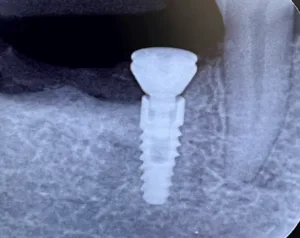

Un implante dental es un elemento utilizado en odontología para reemplazar la raíz de uno o más dientes perdidos. Se trata de un tornillo fabricado en titanio que se coloca directamente dentro del hueso maxilar o mandibular, es decir, en el hueso de la boca. Su función principal es servir como base firme y estable para sostener los nuevos dientes que se colocarán posteriormente. El implante dental no es el diente visible, sino la parte que va dentro del hueso y que cumple el mismo papel que cumpliría la raíz de un diente natural.

El diseño del implante dental está pensado para facilitar su integración con el hueso. Su forma de tornillo permite que se inserte de manera precisa y que el hueso se adapte a su superficie. Esta estructura favorece una fijación firme, lo que resulta esencial para que el implante cumpla correctamente su función como reemplazo de la raíz dental. Una vez integrado, el implante se comporta como un anclaje sólido que no se mueve ni genera molestias en condiciones normales.

En conclusión, un implante dental es un tornillo de titanio que se coloca dentro del hueso de la boca para reemplazar la raíz de uno o más dientes perdidos. Su función es actuar como una base firme y estable sobre la cual se colocarán los nuevos dientes. Gracias a su material y a su diseño, el implante se integra con el hueso y se convierte en una parte fundamental de la estructura bucal. Comprender qué es un implante dental permite entender por qué es una de las soluciones más utilizadas y efectivas para reemplazar dientes perdidos de forma fija y duradera.